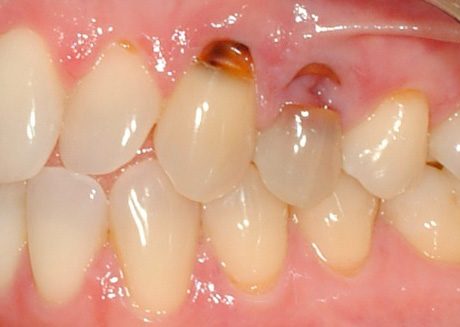

A foto abaixo mostra uma comparação de cárie cervical com cárie radicular:

- Perturbações estéticas visíveis aos olhos. Isso se deve ao aumento da área da lesão e à unificação da cárie na base da raiz com defeitos cervicais. A foto a seguir mostra um exemplo: